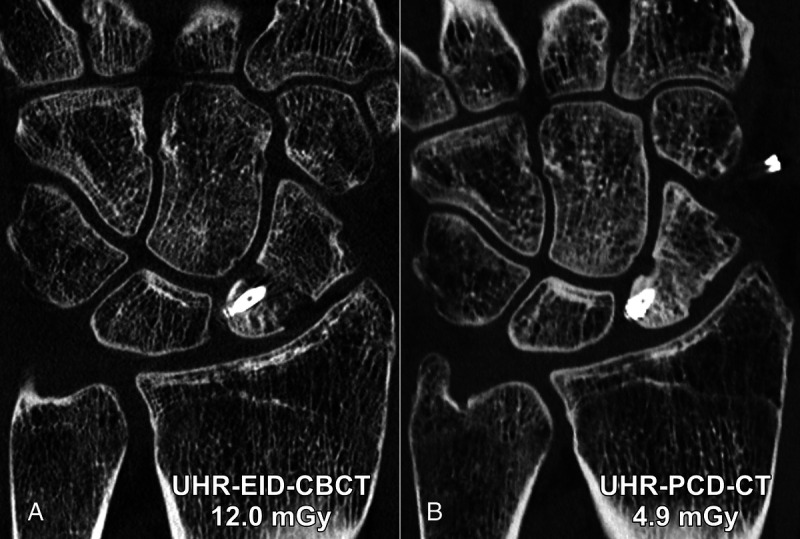

摘要:光子计数探测器(PCD)是近年来医学成像领域最具影响力的技术发展之一。PCD-CT 扫描仪在许多方面都超越了采用能量集成探测器技术的传统系统,可为所有放射亚专科提供卓越的空间分辨率和剂量效率。肌肉骨骼(MSK)成像需要在同一次扫描中详细显示骨小梁微结构和广泛的解剖学覆盖范围,因此 PCD-CT 的卓越性能尤其使其受益匪浅。然而,由于 PCD-CT 为用户提供了大量图像采集和重建的定制选项,因此 MSK 放射科医生需要熟悉该扫描仪,才能充分挖掘其潜力。从基于滤波器的光谱整形以减少全视野超高分辨率扫描的伪影,到单源或双源多能数据的后处理,几乎所有成像任务都可以通过 PCD-CT 的优化方法来完成。本综述旨在概述迄今为止 PCD-CT 在 MSK 成像中最有前景的应用,说明目前的局限性,并强调未来研究和发展的方向。

Abstract: Photon-counting detectors (PCDs) have emerged as one of the most influential technical developments for medical imaging in recent memory. Surpassing conventional systems with energy-integrating detector technology in many aspects, PCD-CT scanners provide superior spatial resolution and dose efficiency for all radiological subspecialities. Demanding detailed display of trabecular microarchitecture and extensive anatomical coverage frequently within the same scan, musculoskeletal (MSK) imaging in particular can be a beneficiary of PCD-CT's remarkable performance. Since PCD-CT provides users with a plethora of customization options for both image acquisition and reconstruction, however, MSK radiologists need to be familiar with the scanner to unlock its full potential. From filter-based spectral shaping for artifact reduction over full field-of-view ultra-high-resolution scans to postprocessing of single- or dual-source multienergy data, almost every imaging task can be met with an optimized approach in PCD-CT. The objectives of this review were to give an overview of the most promising applications of PCD-CT in MSK imaging to date, to state current limitations, and to highlight directions for future research and developments.